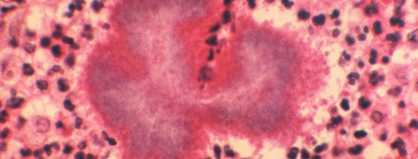

Nocardiosis is a disease caused by bacteria found in soil and water. It can affect the lungs, brain, and skin.